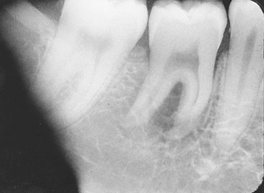

What is the problem with this Elongation X-ray?

Inadequate vertical angulation, Long, distorted teeth

How would you resolve this Elongation X-ray?

Move PID